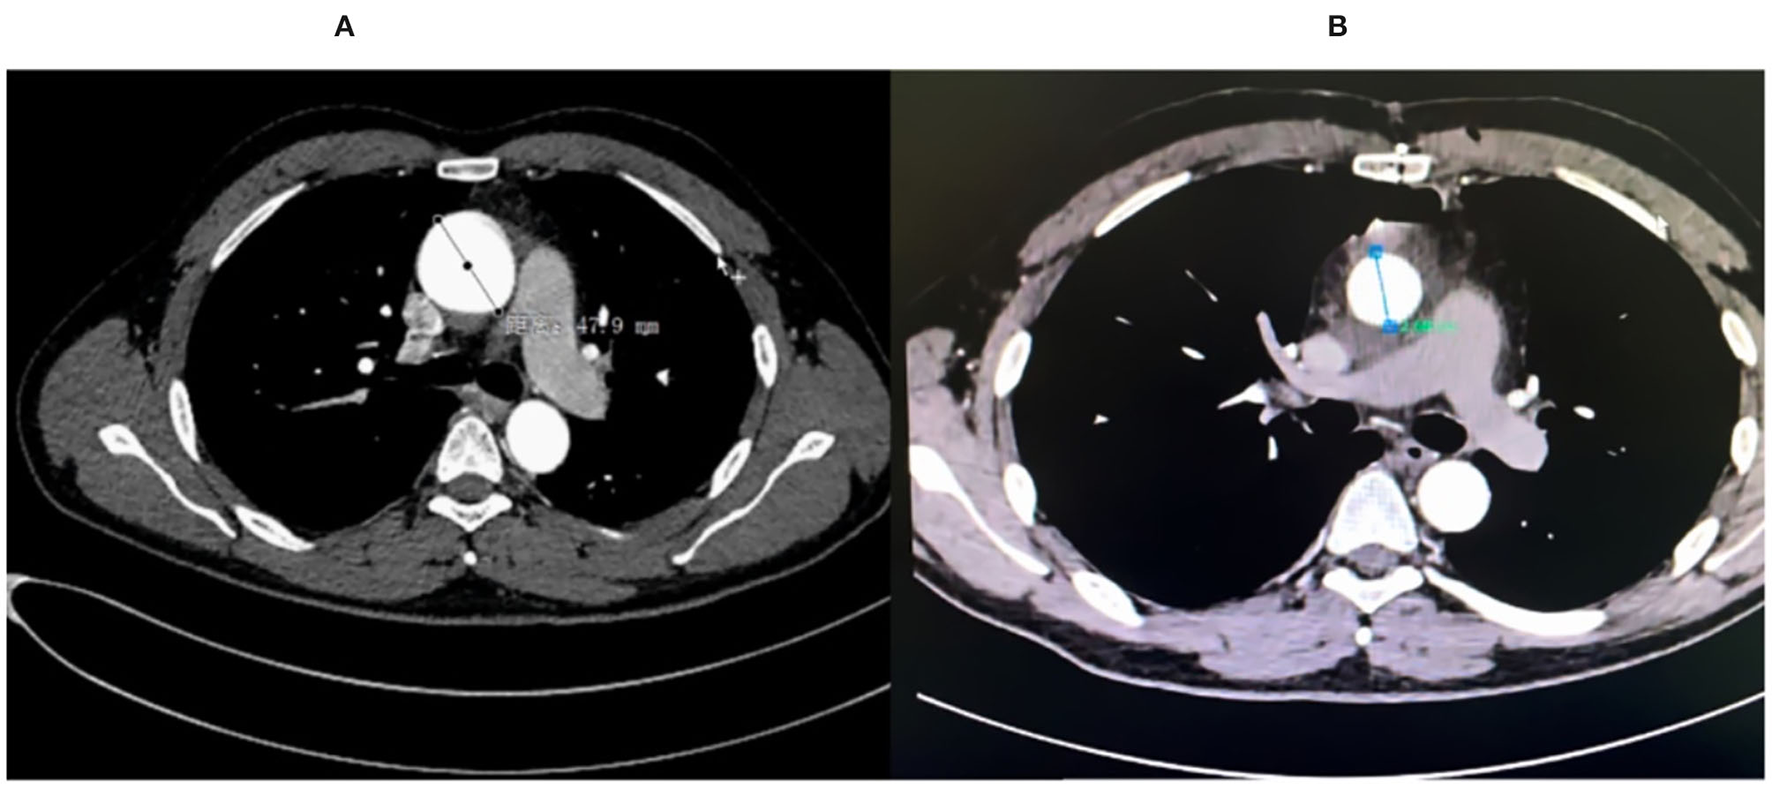

Figure 2

(A) The pre-op CT angiography (CTA) showed ascending aortic aneurysm of 47.9 mm. (B) The post-op CTA scan showed normal ascending aortic size.

A 45-year-old man suffered from a dysfunctional QAV (Hurwitz classification, type B) with severe aortic insufficiency (AI), decompensation heart failure, and intermittent atrial fibrillation. Transthoracic echocardiography (TTE) and transesophageal echocardiography (TEE) indicated a Type B QAV with a dilated ascending aorta of 47.9 mm (Figure 2A). TTE found that the left ventricular end-diastolic diameter was 77 mm and had a reduced ejection fraction of 39%. Modified “tricuspidization” of QAV, an innovative technique, and aortic valve annular banding were utilized to correct aortic valve insufficiency, and the ascending aorta was replaced at the same time.

Heartbeat was reinitiated, and there was no arrhythmia after unclamping. TEE showed that the residual three cusps functioned well without regurgitation or stenosis (Figures 1B,D). The patient recovered uneventfully and was discharged within 2 weeks. A short-term follow-up of 12 months showed no recurrence of AI, and the aortic aneurysm was resolved (Figure 2B). The left ventricle diameter decreased to 51 mm as the EF value increased to 64%. The patient did not experience significant complications or discomfort.